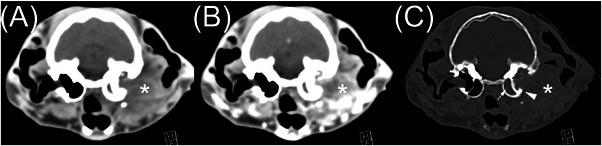

25只患有耳道肿瘤的猫的计算机断层扫描结果。

Computed tomographic findings in 25 cats with ear canal neoplasia.

Computed tomography is commonly used to evaluate feline otic disease; however, published studies characterizing the CT appearance of ear canal neoplasia are limited. The purpose of this multicenter, retrospective, secondary analysis, cross-sectional study was to describe the CT features of histopathologically confirmed feline ear canal neoplasia. The CT studies of 25 cats with ear canal neoplasia were prospectively scored by consensus of two veterinary radiologists. Recorded parameters were the presence of focal or multifocal tissue enlargement (mass/masses), lesion shape, location of the center of mass, attenuation characteristics, features of contrast enhancement, involvement of otic structures, calvarial and brain changes, changes of nearby structures, and lymphadenopathy. There was a significant overlap of CT findings between cats with malignant ceruminous gland neoplasia, ceruminous gland adenoma, and squamous cell carcinoma (SCC). Ceruminous gland adenoma was typically homogeneous in attenuation with homogeneous contrast enhancement and no intralesional fluid accumulations (IFAs) or involvement of adjacent structures. In contrast, SCC consistently had heterogeneous attenuation, heterogeneous contrast enhancement, IFAs, and involvement/invasion of adjacent structures. Malignant ceruminous gland neoplasia had variable attenuation and pattern of contrast enhancement with occasional IFAs and occasional involvement/invasion of adjacent structures. Knowledge of these imaging features will inform the creation of prioritized differential diagnosis lists. However, a biopsy is required to confirm the diagnosis.

摘要

计算机断层扫描常用于评估猫的耳部疾病;然而,已发表的关于耳道肿瘤CT表现特征的研究有限。这项多中心、回顾性、二次分析横断面研究的目的是描述经组织病理学证实的猫耳道肿瘤的CT特征。两名兽医放射科医生通过共识对25只患有耳道肿瘤的猫的CT研究进行前瞻性评分。记录的参数包括局灶性或多灶性组织增大(肿块)的存在、病变形状、肿块中心位置、衰减特征、对比增强特征、耳部结构受累情况、颅骨和脑部变化、附近结构变化以及淋巴结病。恶性耵聍腺肿瘤、耵聍腺腺瘤和鳞状细胞癌(SCC)的猫之间的CT表现存在显著重叠。耵聍腺腺瘤的衰减通常均匀,对比增强均匀,无瘤内液体聚集(IFA)或相邻结构受累。相比之下,SCC始终具有不均匀衰减、不均匀对比增强、IFA以及相邻结构受累/侵犯。恶性耵聍腺肿瘤的衰减和对比增强模式各不相同,偶尔有IFA,偶尔有相邻结构受累/侵犯。了解这些影像学特征将有助于制定优先鉴别诊断清单。然而,确诊需要活检。